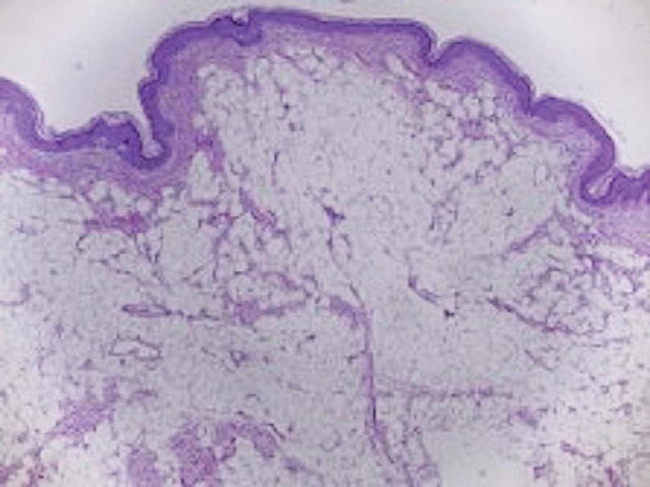

Histologicamente, o nevo cutâneo lipomatoso superficial é caracterizado por acúmulo de adipócitos maduros ectópicos na derme. Quando eles são escassos, apresentam distribuição perivascular com infiltrado linfomonocítico. Quando estão em maior número, essa relação não é tão clara e o limite entre derme e hipoderme torna-se pouco nítido.As fibras colágenas dérmicas encontram-se inalteradas, podendo estar desorganizadas ou com densidade aumentada. Já as fibras elásticas podem estar normais, aumentadas, reduzidas ou até mesmo ausentes.Também foi descrito um aumento de mucina na derme papilar e subpapilar.A epiderme encontra-se normal ou com acantose, podendo conter estruturas comedonianas.13,14 Os apêndices cutâneos não se encontram substituídos. Contudo, alguns casos de NCLS com anomalias pilosas têm sido descritos, como estruturas abortivas germinativas foliculares-símile, unidades pilossebáceas hipertróficas, fibrose perifolicular, fibrofoliculomas e hamartomas císticos foliculossebáceos.8

O exame histopatológico da lesão pedunculada exuberante revelou a presença de tecido adiposo maduro na derme reticular com extensão à derme papilar, caracterizando o diagnóstico de nevo lipomatoso cutâneo superficial (Figura 4). Exames histopatológicos dos nódulos do tronco e membros apresentaram características semelhantes entre eles, revelando tecido adiposo maduro entremeado por alguns capilares congestos, compatível com lipoma (Figura 5).